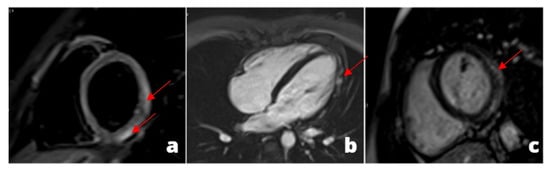

Figure 3.

MINOCA-Miocardial Infarct non obstructive coronaries. The patient presented to the emergency department with acute chest pain, ECG and cardiac enzymes suggestive of STEMI in the lateral wall of the left ventricle. The patient was readily referred to coronary angiography and cardiac catheterization showed absence of obstructive stenoses in the coronary tree (a). One day later a cardiac MRI was performed demonstrating a subacute ischemic scar in the lateral wall of the medium-apical left ventricle ((b)-LGE short axis view, (c)-LGE four chambers view). In the context of transmural late gadolinium enhancement, a constantly hypointense central area is present, representing a microvascular obstruction zone (red arrow). A cardiac CT was subsequently performed in order to assess coronary wall features and the presence of atherosclerosis. CT images in volume rendering (d) and multiplanar oblique reconstruction (e) demonstrated a non-calcified atherosclerotic alteration in an obtuse marginal vessel, serving the infarcted zone. A partly calcified atherosclerotic pathology was present in the anterior descending artery.